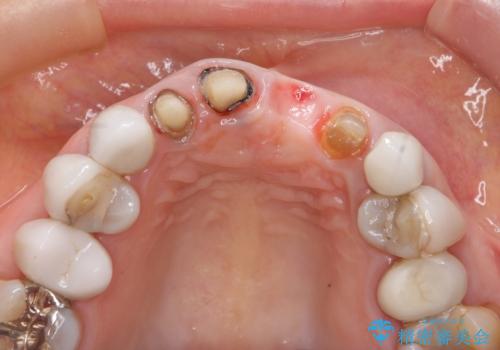

[ セラミック治療 ] 歯ぐきの際の黒ずみを改善したい

- 歯ぐきとセラミックの間の黒ずみが目立つので、きれいに治してほしい。と希望され来院されました。

歯ぐきの位置が変化しクラウン下の歯が見えるようになってしまったことで、審美障害が生じている状態です。

クラウンマージンの再設定を行うことで、黒ずんだ部分を再度覆い、審美障害を改善します。